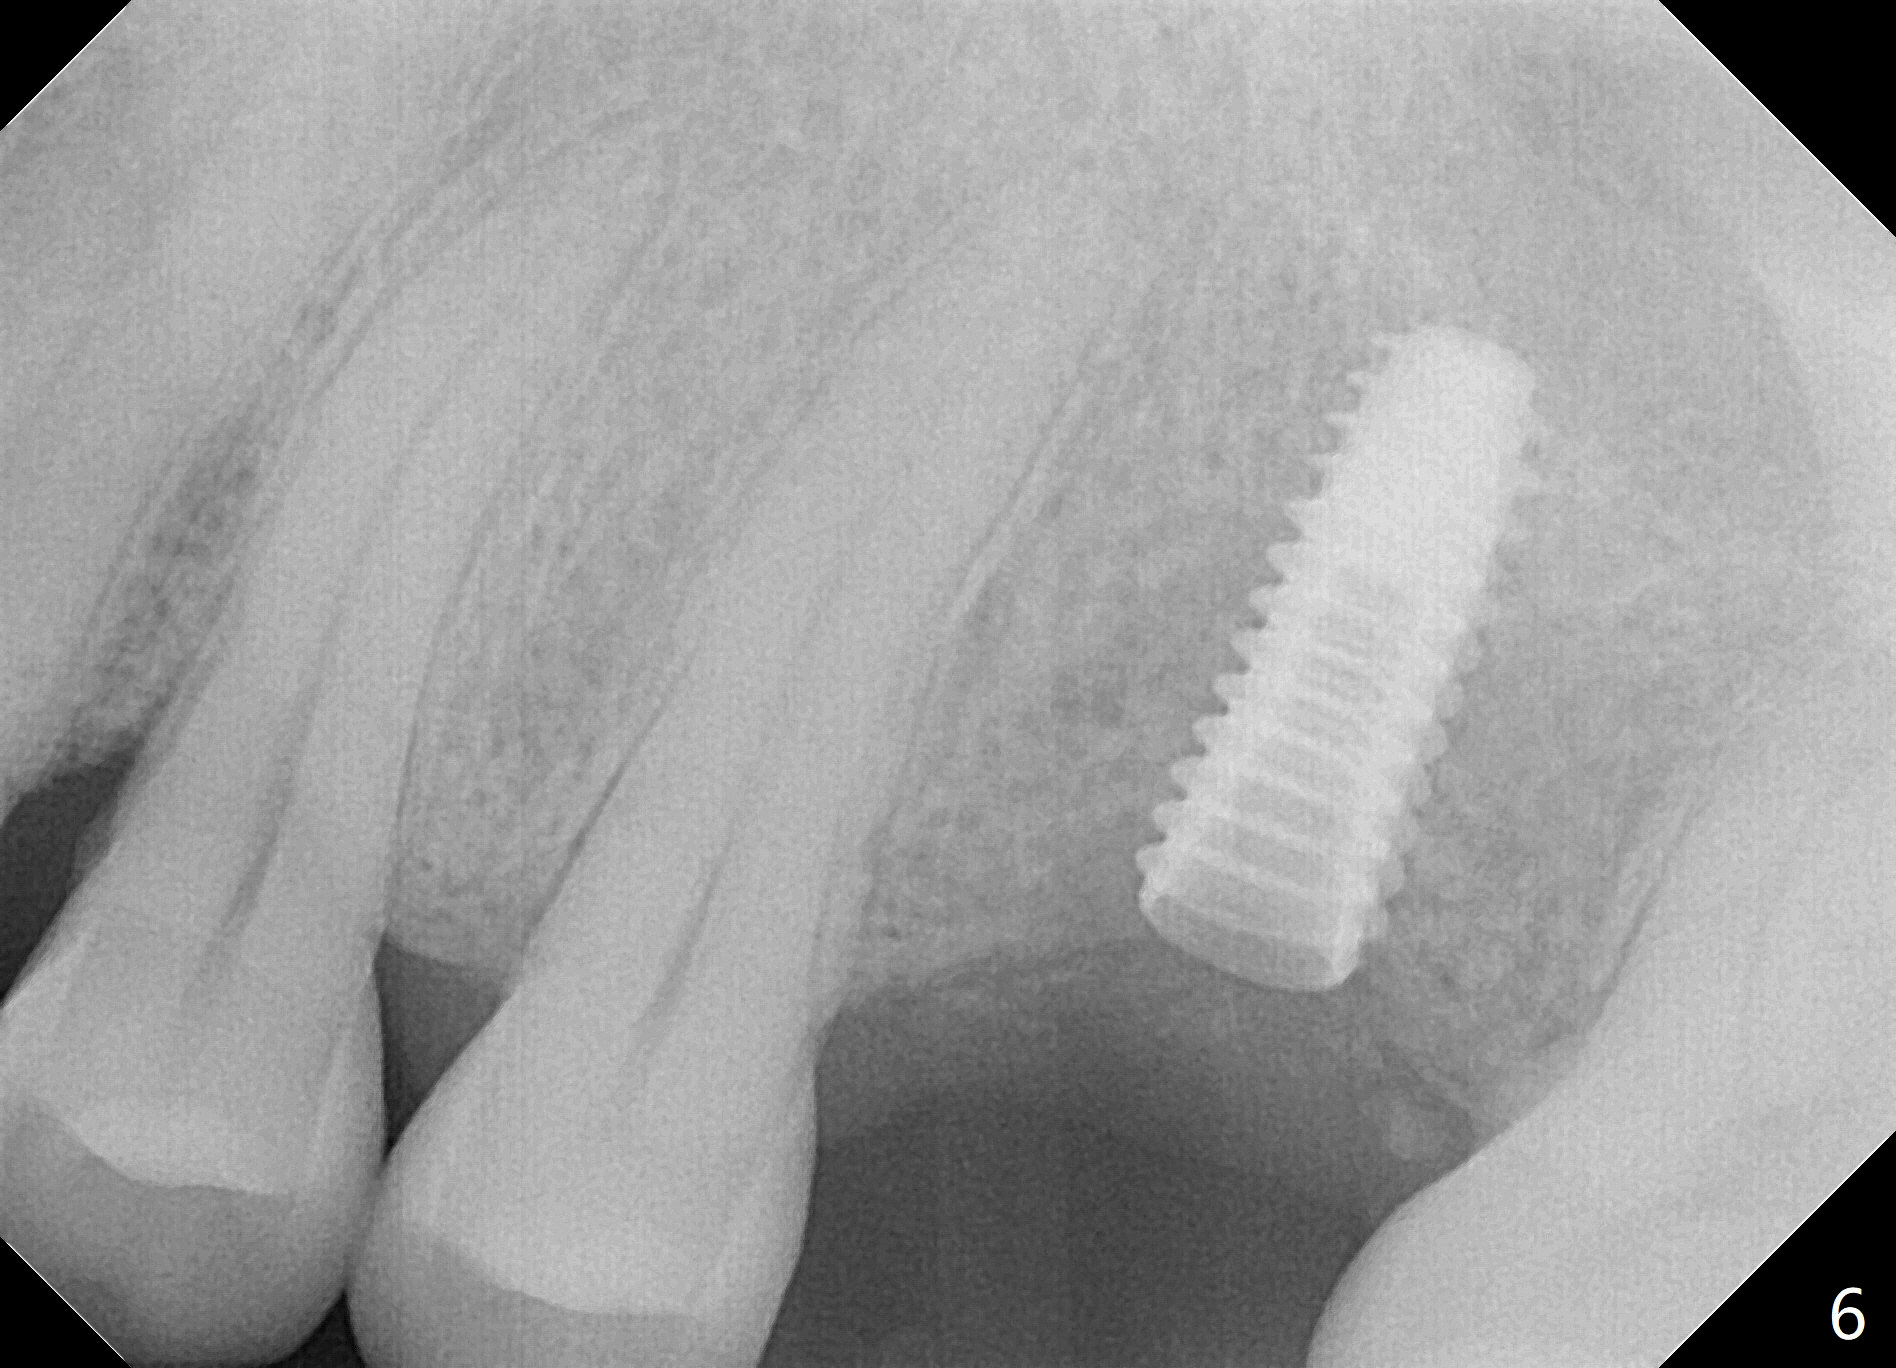

The edentulous area at #14 is moderately atrophic, After incision, the bone is too hard for #15 blade for bone expansion. Osteotomy is initiated with 1.2 mm drill, followed by insertion 1.3/2.3 mm bone expander (Fig.1). Use the same instruments are reused twice to change the trajectory (Fig.2,3). Finally Lindamann bur is utilized to move the osteotomy distally by ~ 2 mm; bone expansion continues until 2.4/3.7 mm expander for 13 mm with 50 Ncm (Fig.4). The last expander 3/4.4 mm barely enters the osteotomy for 6 mm. A 3.7 mm drill has to be used for 12 mm before placement of a 4.5x11.5 mm implant with >35 Ncm (Fig.5). A 5.5x5(3) mm abutment is placed with allograft (<) placed around the implant. Following suturing, periodontal dressing is applied around the implant. The abutment dislodges 3 months postop (Fig.6). Crown is delivered 3 weeks later. The abutment screw is retightened ~ 2 months later. He is a bruxer. The abutment screw is loose again <2 years post cementation (6 months post #18 screw retightenting and occlusal reduction), probably related to distal implant placement (Fig.7).